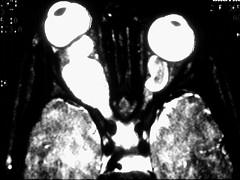

问题 患儿,8岁,因双眼突出,无痛性进展性视力逐渐减退就诊,眼底见视神经萎缩,眼眶CT如图,该患者最可能患 ( )

选项 A、神经纤维瘤 B、以上都不是 C、视神经脑膜瘤 D、视乳头血管瘤 E、神经胶质瘤

答案 E